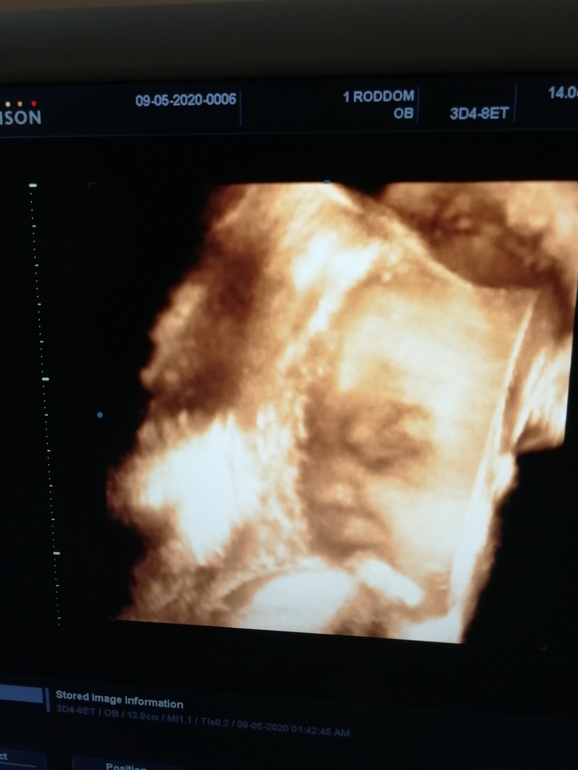

Узист хороший юморной дядька, все показывал и рассказывал, попросила его сделать пару фото на память, как он только не пытался, то одним датчиком, то другим, то на бок меня перевернул, а доча что? доча с характером, 20 минут безуспешно ловили её личико в профиль, так и не далась 🙅🏼♀️ "вы кто такие, я вас не звала!" 😂 Собственно то, что получилось в 3д, по-моему она не довольна

Все детки на 3д такие... не очень симпатичные? 😅